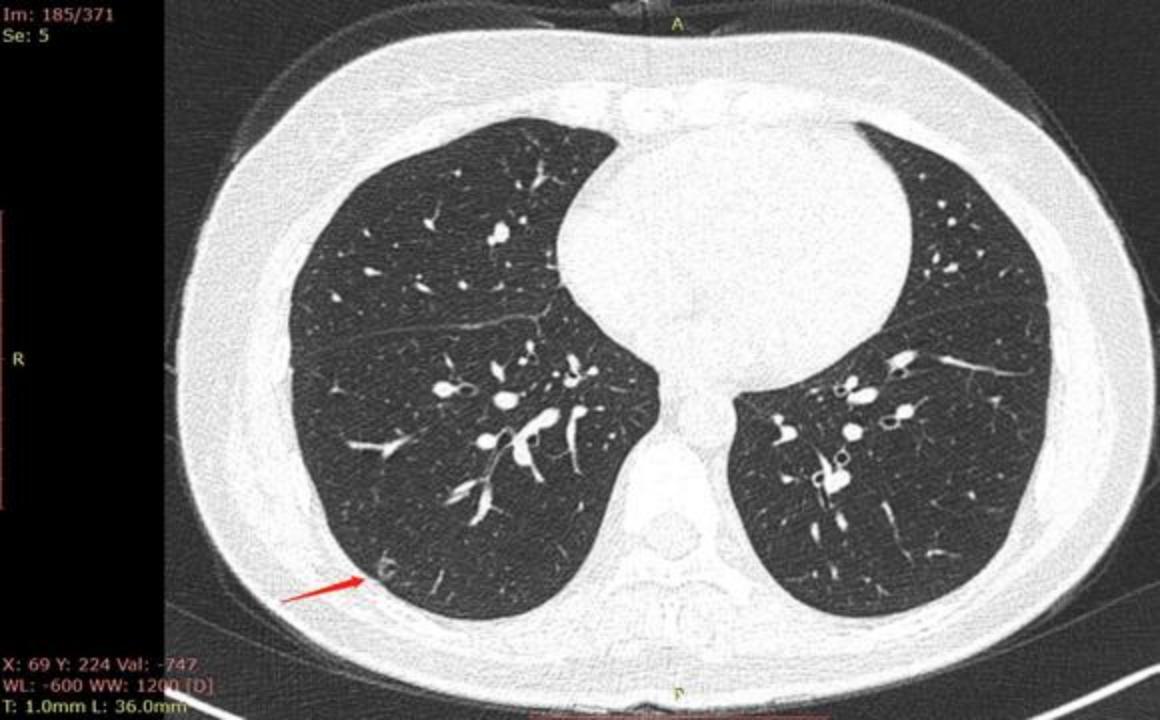

2022年7月29日去同一家A医院复查拍CT,检查结果如下,四个月后,结节从1.2变成了1.9 cm,发现结节长这么快,真的很慌,我老公不抽烟不喝酒,身体一直比较健康,没有住过院都,也没有家族史,不知道一下就长这么大一个结节,求助各位病友,各位医生,还有敬爱的戴主任,麻烦各位有经验的帮忙看看,我们目前只看上一个北京三甲医院普通号的大夫,大夫只说磨玻璃不应该长这么快,长的挺奇怪,不典型,其他没说什么,还没挂上其他医院的号,先麻烦各位帮忙看看,万分感谢!

CT截图: